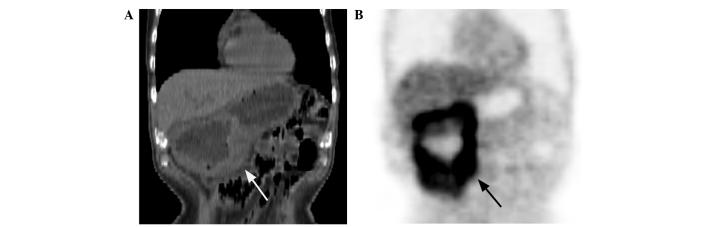

The role of F-fluorodeoxyglucose positron emission tomography/computed tomography (F-FDG PET/CT) in numerous malignant tumors, including gastric lymphoma, is well-established. However, there have been few studies with regard to the F-FDG PET/CT features of gastric lymphoma. The aim of the present study was to characterize the F-FDG PET/CT features of gastric lymphoma, which were compared with those of gastric cancer. Prior to treatment, F-FDG PET/CT was performed on 24 patients with gastric lymphoma and 43 patients with gastric cancer. The F-FDG PET/CT pattern of gastric wall lesions was classified as one of three types: Type I, diffuse thickening of the gastric wall with increased FDG uptake infiltrating more than one-third of the total stomach; type II, segmental thickening of the gastric wall with elevated FDG uptake involving less than one-third of the total stomach; and type III, local thickening of the gastric wall with focal FDG uptake. The incidence of the involvement of more than one region of the stomach was higher in the patients with gastric lymphoma than in those with gastric cancer. Gastric FDG uptake was demonstrated in 23 of the 24 patients (95.8%) with gastric lymphoma and in 40 of the 43 patients (93.0%) with gastric cancer. Gastric lymphoma predominantly presented with type I and II lesions, whereas gastric cancer mainly presented with type II and III lesions. The maximal thickness was larger and the maximal standard uptake value (SUV) was higher in the patients with gastric lymphoma compared with those with gastric cancer. A positive correlation between the maximal thickness and SUV was confirmed for the gastric cancer lesions, but not for the gastric lymphoma lesions. There was no difference in the maximal thickness and SUV of the gastric wall lesions between the patients without and with extragastric involvement, for gastric lymphoma and gastric cancer. Overall, certain differences exist in the findings between gastric lymphoma and gastric cancer patients on F-FDG PET/CT images, which may contribute to the identification of gastric lymphoma.

氟脱氧葡萄糖正电子发射断层扫描/计算机断层扫描(F-FDG PET/CT)在包括胃淋巴瘤在内的众多恶性肿瘤中的作用已得到充分证实。然而,关于胃淋巴瘤的F-FDG PET/CT特征的研究却很少。本研究的目的是描述胃淋巴瘤的F-FDG PET/CT特征,并与胃癌的特征进行比较。治疗前,对24例胃淋巴瘤患者和43例胃癌患者进行了F-FDG PET/CT检查。胃壁病变的F-FDG PET/CT模式分为三种类型之一:I型,胃壁弥漫性增厚,FDG摄取增加,浸润超过全胃的三分之一;II型,胃壁节段性增厚,FDG摄取增加,累及全胃不到三分之一;III型,胃壁局部增厚,有局灶性FDG摄取。胃淋巴瘤患者胃多区域受累的发生率高于胃癌患者。24例胃淋巴瘤患者中有23例(95.8%)出现胃FDG摄取,43例胃癌患者中有40例(93.0%)出现胃FDG摄取。胃淋巴瘤主要表现为I型和II型病变,而胃癌主要表现为II型和III型病变。与胃癌患者相比,胃淋巴瘤患者的最大厚度更大,最大标准摄取值(SUV)更高。在胃癌病变中证实最大厚度与SUV之间存在正相关,但在胃淋巴瘤病变中未证实。对于胃淋巴瘤和胃癌,有无胃外受累患者的胃壁病变最大厚度和SUV无差异。总体而言,胃淋巴瘤和胃癌患者在F-FDG PET/CT图像上的表现存在一定差异,这可能有助于胃淋巴瘤的识别。